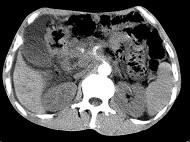

问题 女,50岁,中上腹疼痛,消瘦乏力,影像检查如下图,最佳的诊断是()

选项 A.慢性胰腺炎 B.急性胰腺炎 C.胰腺癌并腹膜后淋巴结转移 D.胰岛素瘤 E.腹膜后淋巴瘤

答案 C